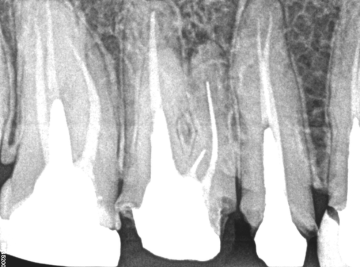

Dente 16 – Remoção de peça, pino metálico, limas fraturadas nos canais mv, mv2 e dv.

Neste caso específico há três partes de um pino metálico, que se partiu, aumentando ainda mais, a utilização das técnicas que foram implementadas. Vejam os passos nas fotos acima.